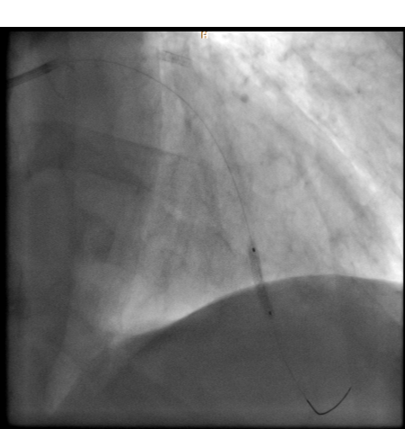

New diffuse spasm proximal to new dLAD stent, retrograde flow to PDA, LCx spasmIVUS: stent under-expansion at LM and pLADSevere spasm at m-dRCA, given IC GTNThen new focal spasm at pRCA and RCA, put on IV GTN infusion